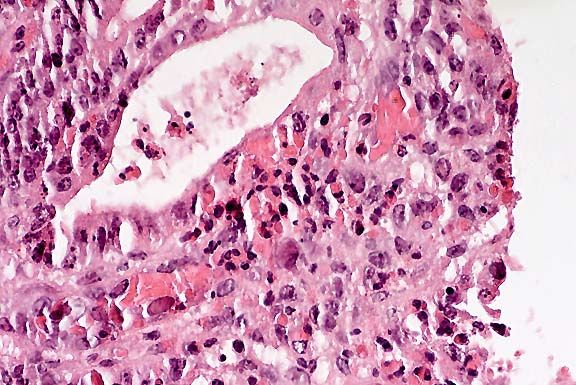

Histology: There is multifocal, nodular to bridging fibrosis of the portal areas with increased numbers of bile ducts and small, congested vessels. Within the fibrous stroma are multiple necrotic foci with large numbers of eosinophils, fibrin, cellular debris, mineral, and numerous oval eggs with a thick, light yellow wall that measure up to 90 x 140 :m in diameter. Many of the eggs are collapsed and defined by a partially disrupted wall that contains mineralized and proteinic globular material. The necrotic foci, eggs, and mineral are surrounded by multinucleated giant cells and epithelioid macrophages that blend into a peripheral zone of fibrovascular tissue with infiltrates of eosinophils, macrophages, plasma cells, lymphocytes and neutrophils. Interspersed with the inflammatory exudate and fibrous stroma is abundant, black granular pigment that is birefringent and yellow-orange with polarized light, consistent with fluke pigment (iron-porphyrin pigment). The surrounding portal areas have mild to moderate multifocal infiltrates of eosinophils, lymphocytes and plasma cells that are often associated with periductal fibrosis and transmigration of the inflammatory cells into the biliary lumina. There is multifocal necrosis and proliferation of plump hyperplastic biliary epithelial cells that surround small numbers of parasite eggs, epithelioid macrophages and multinucleated giant cells in the bile duct lumina.

Contributor's Diagnosis and Comments: Severe multifocal eosinophilic granulomatous cholangiohepatitis with intralesional trematode eggs and pigment.

Etiologic diagnosis: Hepatic fascioliasis, compatible with Fasciola hepatica.

Case 13-1. Liver. Fluke tract contains dark pigment, numerous granulocytes and a golden-brown trematode ovum of Fasciola hepatica within a multinucleated giant cell. 10X

AFIP Diagnosis: Liver: Hepatitis, portal and periportal, granulomatous, eosinophilic, multifocal, severe, with extensive fibrosis, mineralization, dark brown to black granular pigment, and operculated trematode eggs, breed unspecified, bovine.